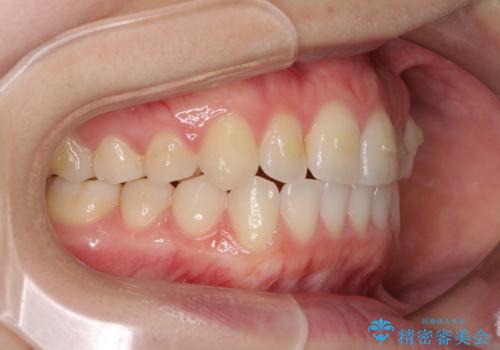

前歯のクロスバイトをインビザライン矯正で改善

- 前歯のデコボコと上下のクロスバイトを気にして来院された患者様です。

インビザラインを用い、IPR(歯と歯の間を削る)と歯列全体を拡大させることで、歯並びを整えていくこととしました。

上の前歯が下の前歯を乗り越える際、奥歯がほとんど咬めない時期があり、乗り越えた後も、インビザライン特有の奥歯の咬みにくさが続きました。

咬み合わせ改善のために治療期間を要しましたが、最終的に奥歯はしっかりと咬めるようになりました。